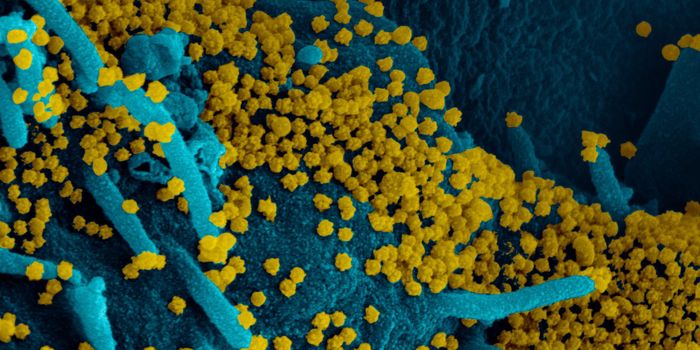

SEP 01, 2021MicrobiologyIt's been generally assumed that people who get infected with SARS-COV-2 will develop antibodies to the virus, which cau ...

APR 20, 2020Cell & Molecular BiologyThe SARS-CoV-2 virus causea huge range of symptoms, and researchers are learning more about the worst cases, which may h ...